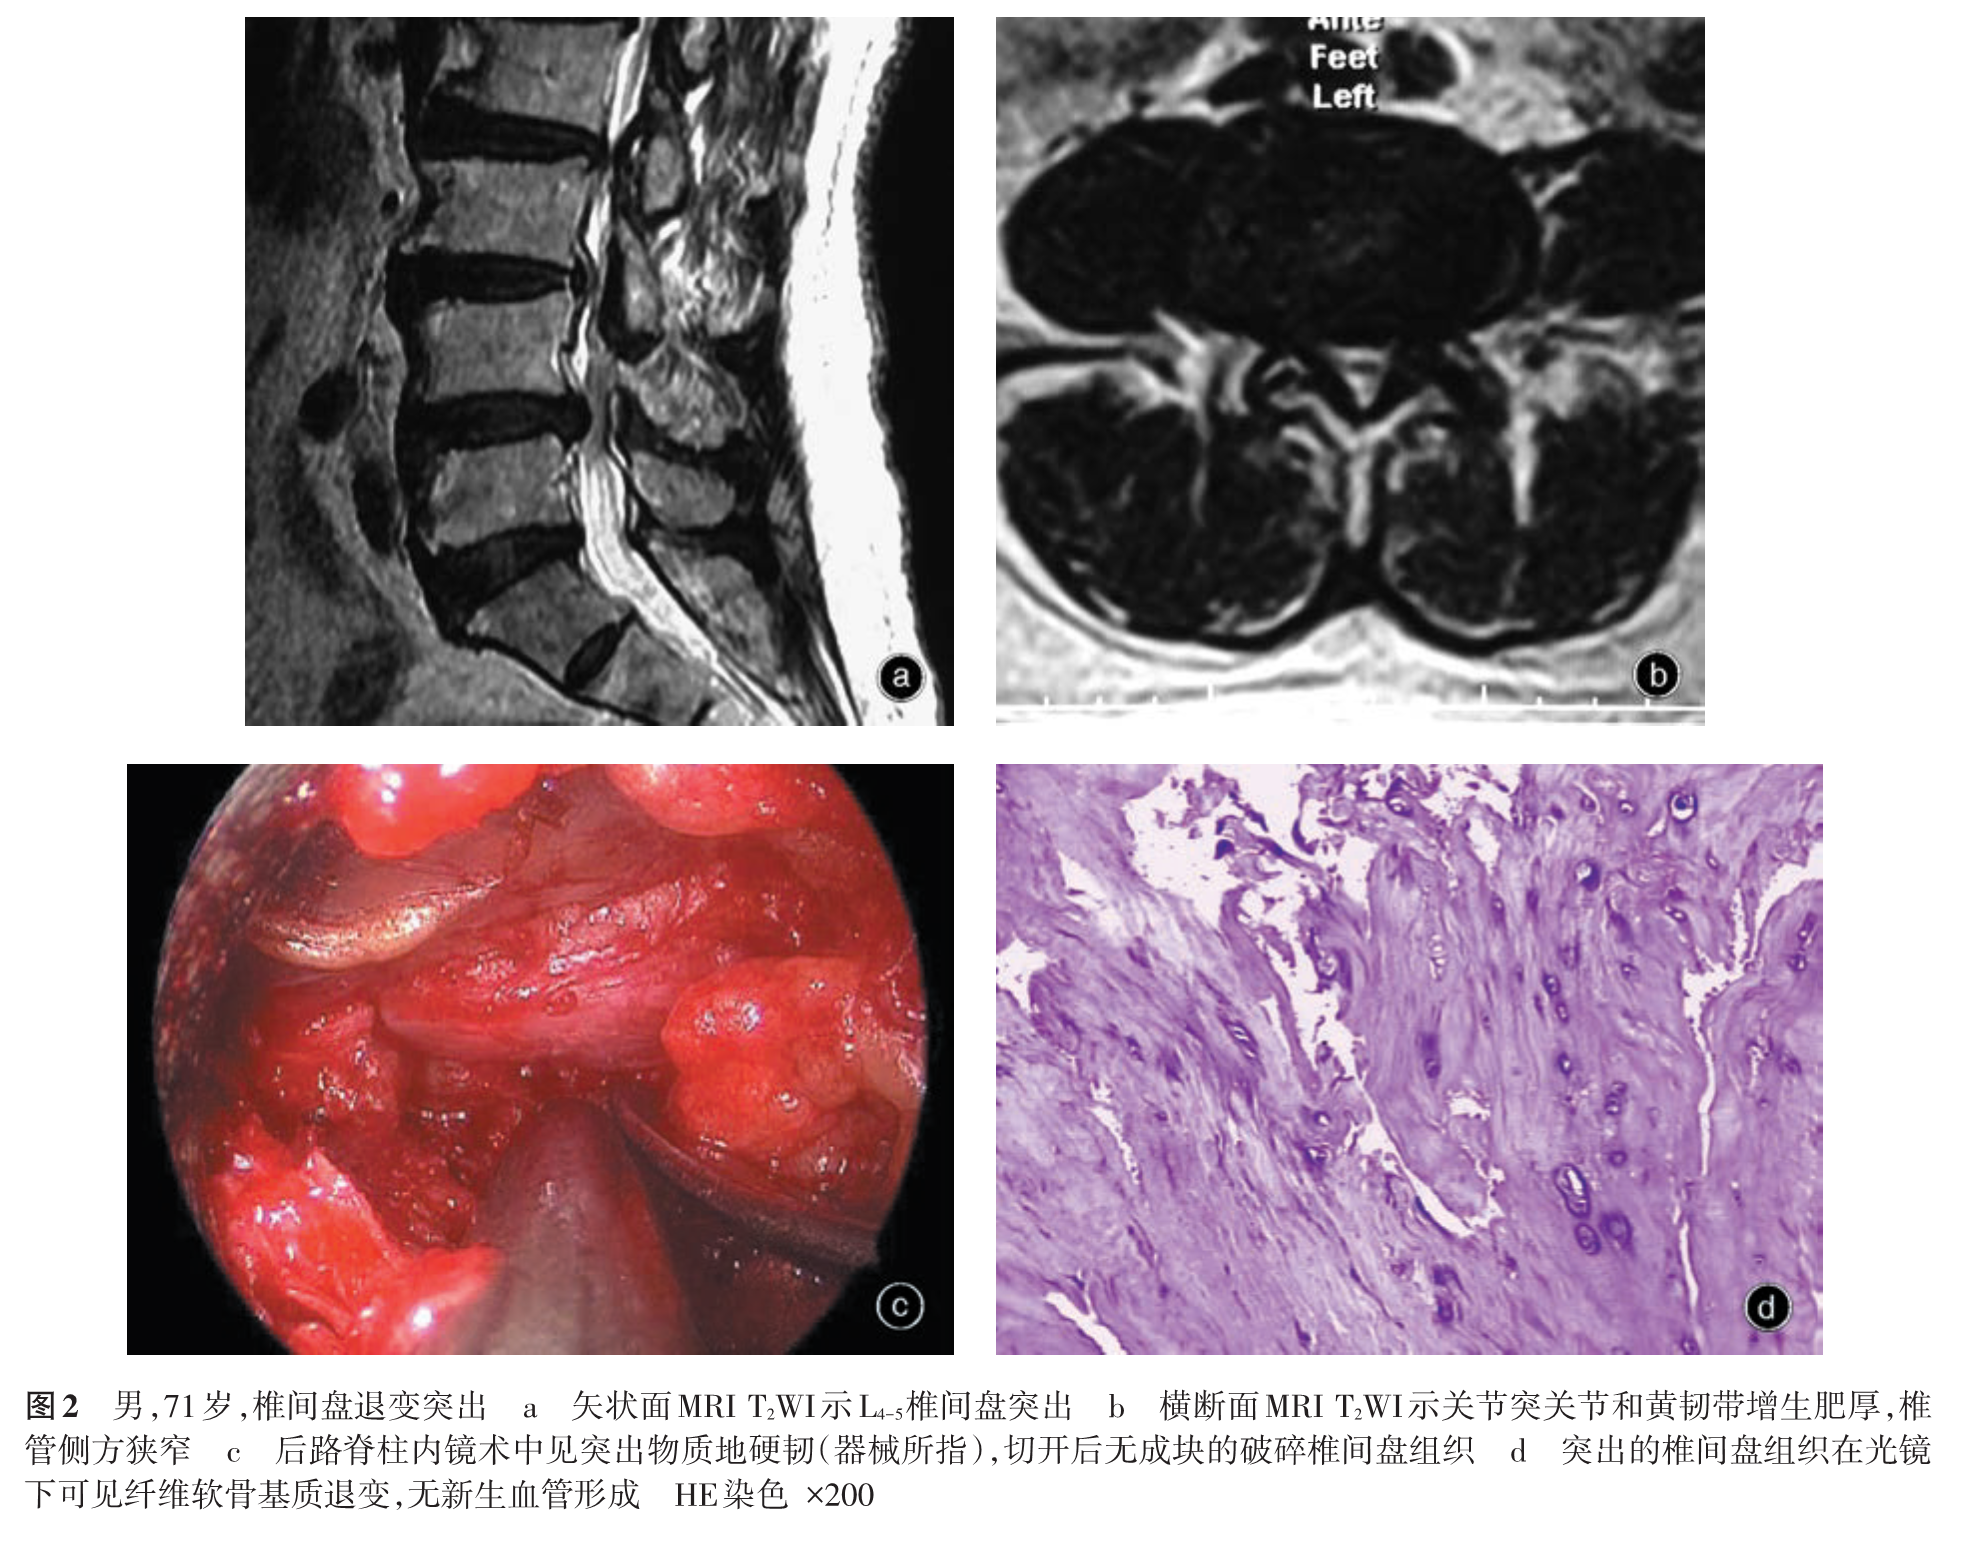

我们在临床实践中发现腰椎间盘突出症在大体病理、免疫学等方面存在较大差异,病变周围组织也有不同的病理改变,存在不同的发病机制,其治疗措施包括手术方法因不同的病理变化而有所差异。基于以上认识,我们在以往分类方法的基础上提出一种新的腰椎间盘突出症病理学分型,分为损伤疝出型、退变突出型、椎体后缘骨软骨病伴椎间盘突出和椎间盘囊肿四型[5-11],并建议根据不同的病理类型进行临床评估,包括手术方法的选择。